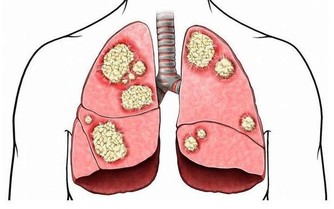

雖說懶不是病,但有時候,懶起來也要人命!這不是危言聳聽,一旦被“懶”附身,許多疾病,包括癌症都將接踵而至。

這6件事偷懶不做,癌症悄悄找上門!